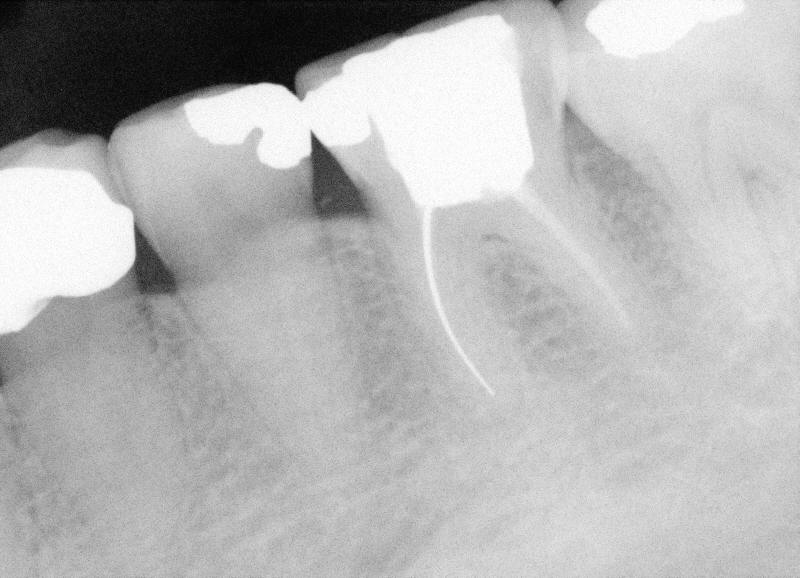

Forty-eight-year-old lady has multiple restoration.  One day she returned to clinic, requesting extraction of #19 because of chip.  "I am not comfortable with that tooth anyway".  She has lived in China, Germany and USA.  She cannot recall the history of treatment involving #19.  Positive finding is mild percussion.  We have taken multiple PAs for #19.  They all look like the one on the right.  It appears that one of mesial canals is missing.  It must be difficult to remove silver cone for RCT retreat.  The patient is ready for implant.  It seems that the tooth is nonsalvageable.

Treatment plan is to extract the tooth atraumatically by sectioning and place an implant in 6 weeks.